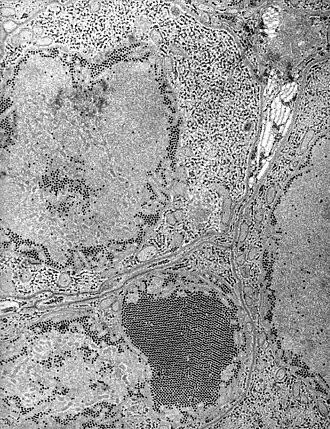

Description de l'image St. Louis Encephalitis (SLE) virus EM PHIL 1871 lores.JPG.

Causes St. Louis encephalitis virus (d)